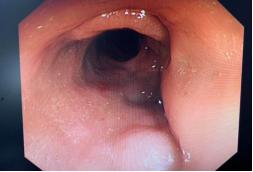

女性,63岁,因“阴道内有粪样分泌物5月余”入院,患者5月前无明显诱因出现腹部疼痛,伴有低热,后出现阴道排气和粪性分泌物,予以抗炎治疗后稍有好转,于外院诊断为直肠阴道瘘,转我院就诊。患者既往子宫切除术手术史,阑尾手术史,拟诊直肠阴道瘘。入院体格检查提示腹软、下腹轻压痛,无反跳痛,肛门指检未见异常;消化道造影提示乙状结肠阴道瘘(图3-1),肠镜示乙状结肠多发憩室(图3-2)。考虑乙状结肠憩室穿孔致乙状结肠阴道瘘,予以保守治疗,包括禁食、肠外营养支持、生长抑素抑制肠液分泌等对症治疗,经治疗后患者未见明显阴道内排气排液,2周后好转出院。

图3-1 肠镜可见结肠憩室